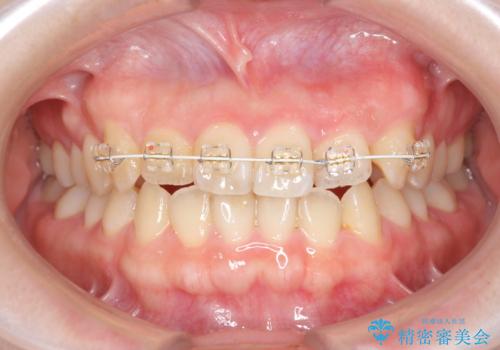

前歯のねじれを改善 小矯正+マウスピース矯正インビザライン

- 「前歯のねじれ、見た目を改善したい。」と矯正治療を希望され来院されました。

マウスピース矯正では改善の難しい前歯のねじれを前歯の部分ワイヤー矯正で改善したのち、インビザライン矯正を行い歯列を整えます。

インビザラインを行う前に前歯の部分矯正を行ったことで、しっかりとねじれが取れ整った歯列へと仕上げることが出来ました。